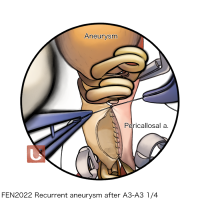

FEN2022シリーズ